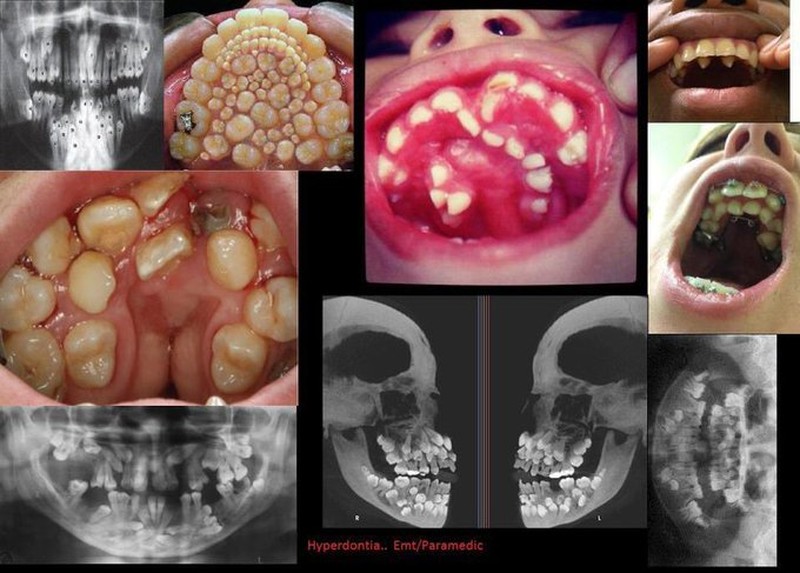

Hyperdontia atau supernumerary teeth adalah kondisi yang membuat pengidapnya mengalami kelebihan gigi di mulut. Foto: Twitter/creepy_org